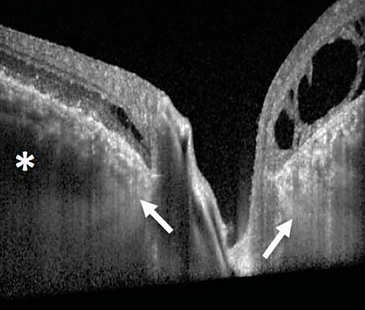

Primary Open Angle Glaucoma

A group of ocular disorders of multi-factorial aetiology, united by a clinically characteristic optic neuropathy with potentially progressive clinically visible changes at the ONH, comprising focal or generalised thinning of the neuroretinal rim with excavation and enlargement of the optic cup, representing neurodegeneration of the of the retinal ganglion cell axons and deformation of the lamina cribrosa. Corresponding diffuse and localised nerve-fibre-bundle pattern visual field loss may not be detectable in early stages; while VA is initially spared, progression can lead to a full loss.